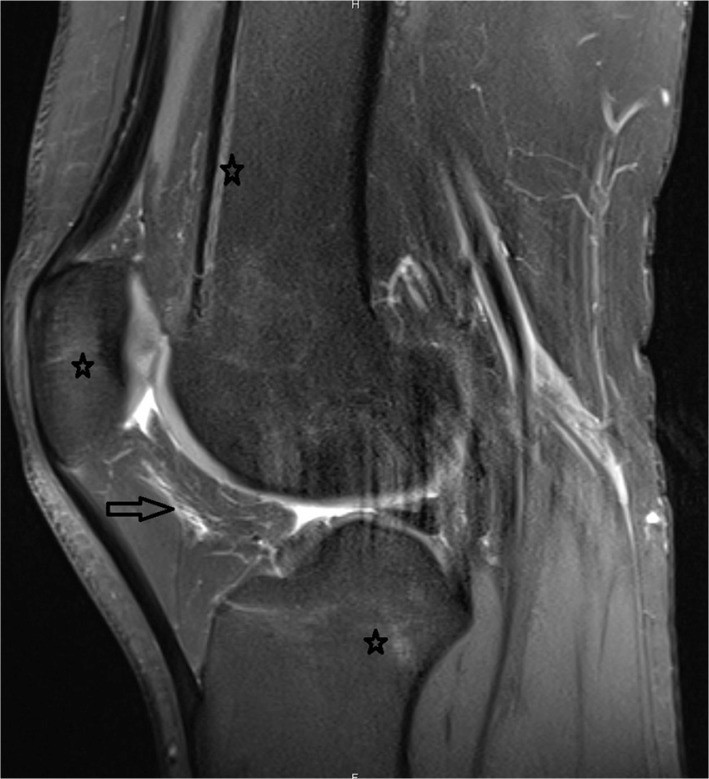

Пример: снимок колена 27-летней женщины без симптомов, занимающаяся кенгу-джампингом. Проксимальная звездочка показывает продольный отек костного мозга (BME) бедра, средняя звездочка показывает BME надколенника, дистальная звездочка показывает BME тибиофеморального сустава. Стрелкой показан отек поднадколенниковой жировой ткани. Тендинопатия надколенника и четырехглавой мышцы проявляется как изменение сигнала в месте их прикрепления.

Наиболее важным результатом, который исследователи наблюдали на МРТ-снимках коленей кенгу-джамперов, был отек костного мозга (BME). Большинство травматических BME колена коррелируют с механизмом повреждения колена. Также исследователи отметили влияние повторяющихся прыжков на переднюю часть бедренной кости и сухожилия разгибателей, в частности при приземлении.